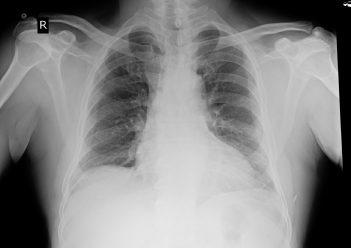

RS :

Position of trachea: central

Bilateral decreased air entry +